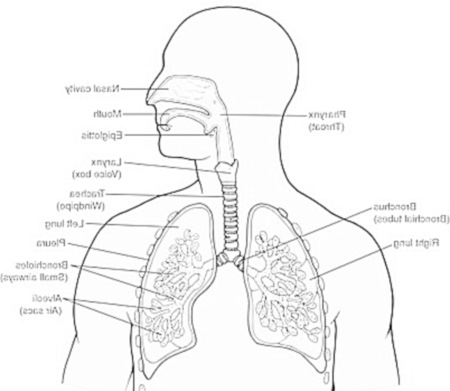

E ‘ facile pensare di avere un sano sistema respiratorio, quando si dà per scontato che la respirazione avviene quasi automaticamente. Tuttavia, anche una leggera diminuzione della funzione polmonare può causare disordine per tutto il resto del corpo e un declino globale nella vostra salute. Ci sono alcuni fattori che possono causare una riduzione della funzione polmonare; tuttavia, è possibile adottare misure per aumentare la salute del vostro sistema respiratorio e aiutare a prevenire la disfunzione.